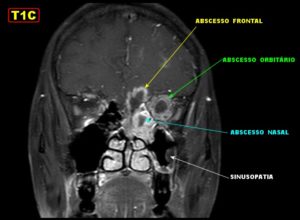

- информативнее других методов обнаруживают сфеноидит компьютерная или магнитно-резонансная томография;

- при недоступности КТ и МРТ выполняется рентгенологическая диагностика;

КТ — исследование пазухи с помощью рентгеновского излучения. КТ позволяет выявить аномалии синуса, степень поражения слизистой. При исследовании с помощью КТ определяется уровень гноя в пазухе.

Ещё более информативным методом диагностики является МРТ — она выявляет послойные поражения, которые могут быть не замечены на КТ.

Единственными методами, которые наверняка могут определить сфеноидит, являются компьютерная томография (КТ) или магнитно-резонансная томография (МРТ) –